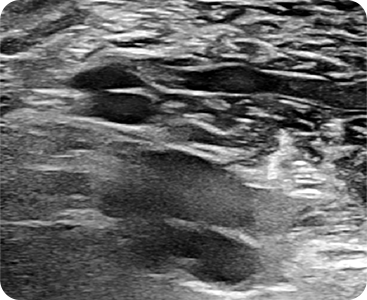

초음파 정밀분석으로 근육의 깊이, 형태, 혈관 분포를 실시간으로 파악하며

정밀하게 단 하나의 근육만을 타겟팅하는 프리미엄 보톡스 시술 방법

초음파 정밀분석

초음파를 통해 육안으로 확인

근육, 혈관 구조 실시간 모니터링

근육 위치와 깊이 실시간 정밀 분석